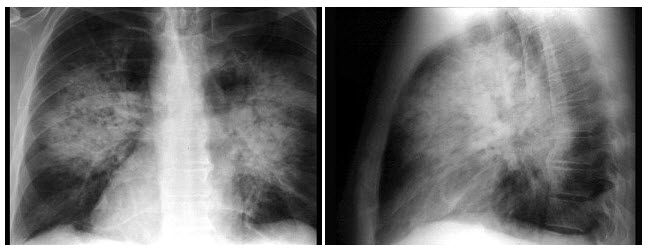

31、单项选择题

男,29岁,体检胸片如图,最可能的诊断是()

A.右上肺炎症